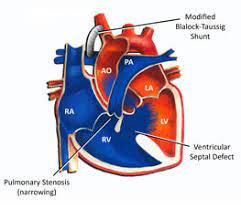

Value added benefits of the B.T. Shunt:

Ø Doctor consultation charges

Ø Lab tests and diagnostic charges

Ø Room charges inside hospital during the procedure

Ø Surgeon Fee

Ø Nursing charges

Ø Hospital surgery suite charges

Ø Anesthesia charges

Ø Routine medicines and routine consumables (bandages, dressings etc.)

Ø Food and Beverages inside hospital stay for patient and one attendant.